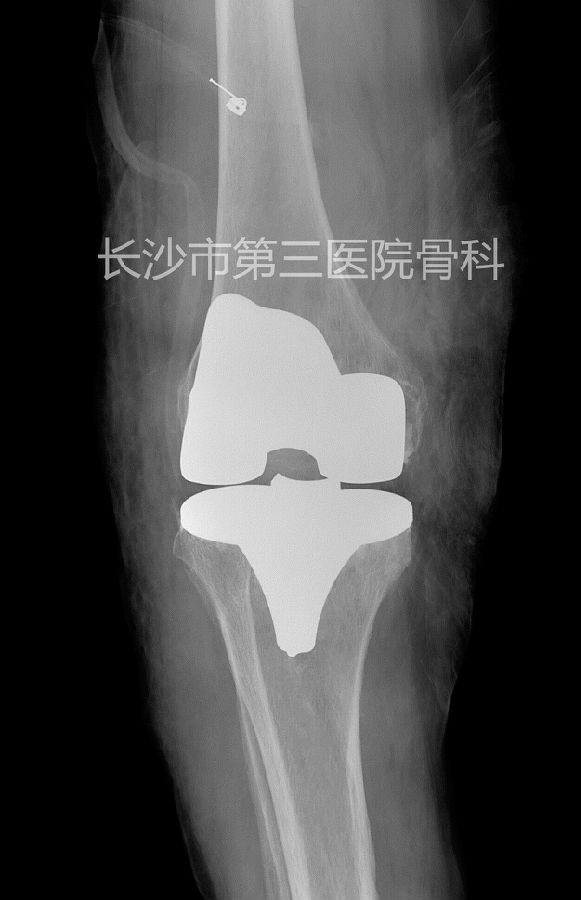

术后影像学资料:

此次3D打印技术联合计算机辅助设计数字化改良膝关节导航模板为新的设计思路及理念,成功为患者实施手术,术后多项数据表明,其较改良前的导板精度更高,术中固定好且不变形,分离软组织少,手术时间进一步缩短,切实可行,较计算机导航辅助技术等更加经济实用,定位准确,无导航技术机械定位失败风险。

在数字化改良膝关节截骨导板下全人工膝关节置换手术的实施标志着长沙市第三医院膝关节置换手术在自主创新方面步入了一个新的台阶,下肢力线的正确重建、假体的准确置入、屈伸间隙和韧带平衡等方面获得了满意的效果,其优点明显:导板材料可以高温高压消毒,手术操作方法简单,降低对术者的技术及经验要求,降低学习曲线,尤其在关节严重畸形,髓内定位系统难以确定其力线的特殊病人中不侵犯股骨侧髓腔,降低出血、感染、脂肪栓塞的风险,可让更多的该类病人得到良好的诊治并获得更为满意的临床疗效。